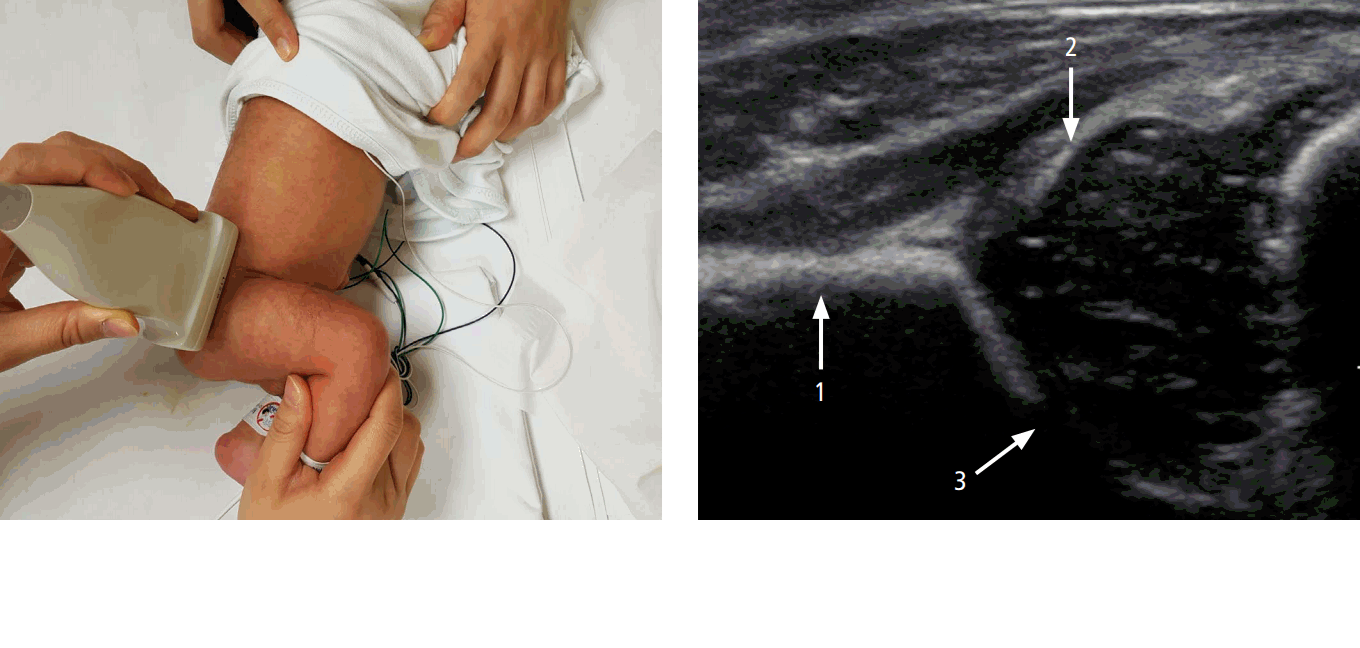

Ako vyšetrenie prebieha?

Vyšetrenie prebieha v pokojnej atmosfére a trvá približne 5-10 minút.

Pozostáva z dvoch častí:

Klinické vyšetrenie

Lekár posúdi symetriu dolných končatín, rozsah pohybu v bedrových kĺboch a vykoná špeciálne testy stability.Ultrazvukové (USG) vyšetrenie

Pomocou USG sondy sa zobrazí zrelosť bedrového kĺbu, tvar jamky a uloženie hlavice stehennej kosti. Vyšetrenie je úplne bezpečné a bezbolestné.